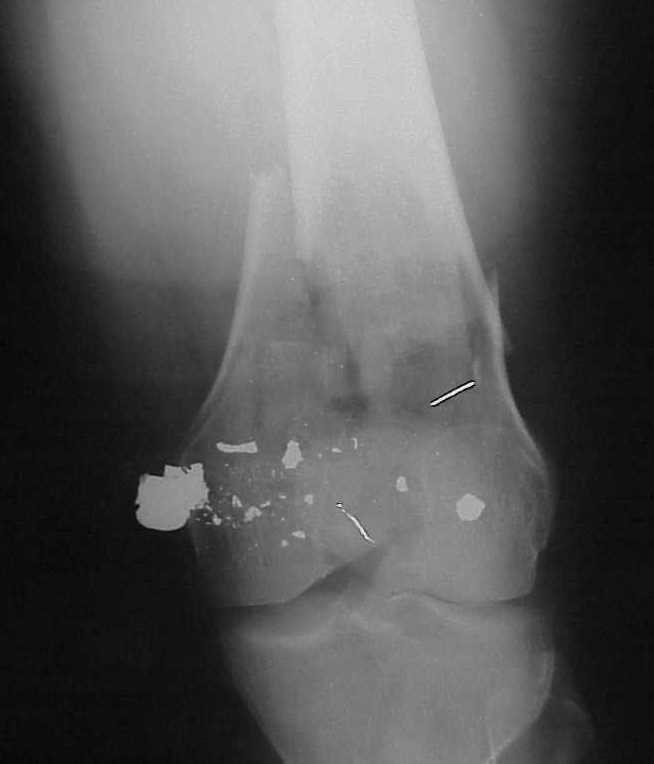

A CT and knee xrays would help identify lateral condyle comminution and/or a "hoffa fragment" of the posterior condyle. I am concerned that the lateral cortex is not sufficient to give purchase for a retrograde IMN. blocking screws could improve this as a possibility. A long blade or LISS if avaible would be my secondary choices. Good luck. Any chance you can get these cases transferred earlier when it

Use 6.5 mm cannulated screws if you have and

place one anterior to where IMN will go if anterior cortex if insufficient and AP screws on either side of the IMN out of the trochlea to provide some additional varus/valgus stability. I worry about the leg going into valgus w/the lack of lateral cortex.

See attached case that was done several years ago before LISS. He had comminuted trochlea and anterior blocking screws were used to prevent anterior IMN cut-out.